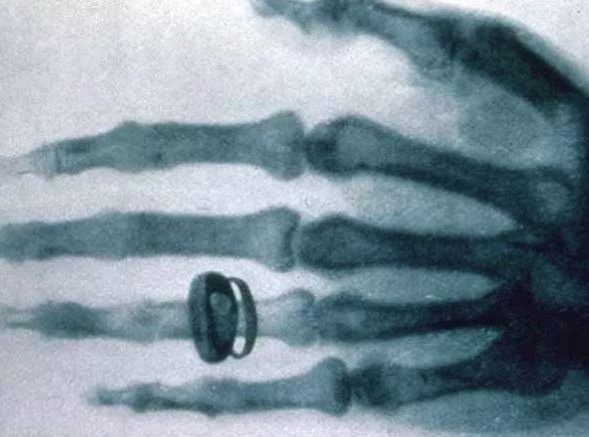

인류 최초의 X선 사진

그 때, 뢴트겐은 진공관에서 몇 피트쯤 떨어진 벤치에서 희미한 발광이 있는 것을 알아차렸다. 당연히 그는 여러 번 방전을 시켜보았고, 매번 발광이 일어나는 것을 확인했다. 그는 그 빛이 나중에 쓰려고 둔 바륨-시안화백금산염 스크린이 있는 곳에서 온 것임을 발견했다. 그는 그것이 새로운 종류의 광선일 것이라고 추측했다. 11월 8일은 금요일이었고, 그는 주말동안 실험을 반복하고 논문을 작성할 수 있었다. 그 다음 주에 그는 실험실에서 먹고 자면서, 그 원인을 규명할 수 없다는 뜻에서 X선이라고 임시로 이름붙인 새로운 광선의 특징들을 연구하였다. 물체들은 어느 정도 차이를 보이지만 이 '새로운 광선'을 투과시킨다는 사실을 알아냈다. 또 엑스레이가 사진건판을 감광시키며, 반사하거나 굴절하지 않는다는 것, 자기장 속에서도 굽어지지 않는다는 것, 음극선이 유리벽이나 반대편 양극에 부딪칠 때 이 빛이 나온다는 것 등을 알아냈다. 새로운 광선은 뢴트겐 광선(Röntgen Rays)이라고 불렸지만, 뢴트겐은 X선라는 용어를 선호했다.

뢴트겐은 논문 “새 종류의 광선에 대하여(On A New Kind Of Rays(Über eine neue Art von Strahlen))”는 X선 발견 50일 후인 1895년 12월 28일에 출판되었다. 1896년 1월 5일에, 오스트리아의 신문에 뢴트겐이 새로운 방사선을 발견한 것이 실렸다. 뢴트겐은 뷔르츠부르크 대학의 명예 의학박사학위를 받았다. 그는 1895년부터 1897년까지 X선에 대한 총 3편의 논문을 썼다. 현재 뢴트겐은 진단방사선학(diagnostic radiology)의 아버지로 불린다.